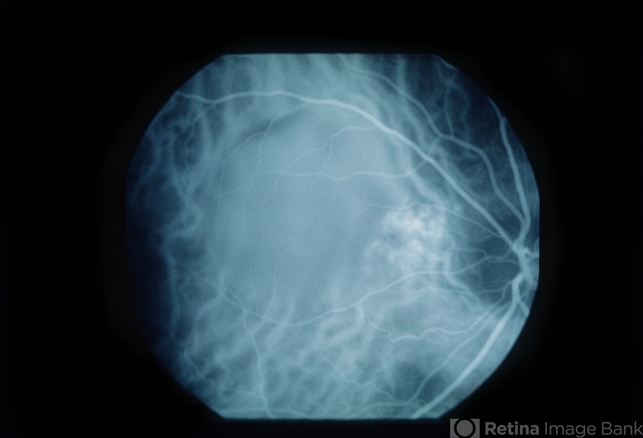

- Large Pigment Epithelial Detachment

- A 41 year old white woman presented with decreasing vision in her right eye over a four month period. Her visual acuity was 20/400 right eye, and 20/20 left eye. Ophthalmoscopy showed a large pigment epithelial detachment with overlying subretinal fluid in the right eye.